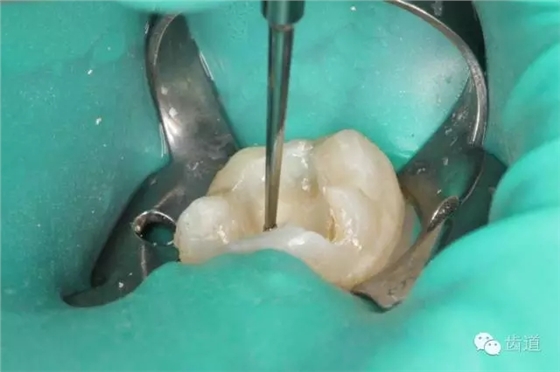

四診(2015.03.10): 主訴:復(fù)診,癥狀消失,無(wú)不適。 檢查:37暫封無(wú)缺損,探痛-,叩痛-,松動(dòng)-,牙齦無(wú)紅腫。 治療過(guò)程: 37橡皮障放置,去盡暫封,超聲清理洞形,試戴嵌體就位,分別處理嵌體及牙體粘結(jié)面,粘固,光照固化,調(diào)整咬合,修整拋光。

2. 超聲清理去除暫時(shí)充填物

3. 試戴嵌體就位良好

10. 術(shù)后即刻口內(nèi)照片